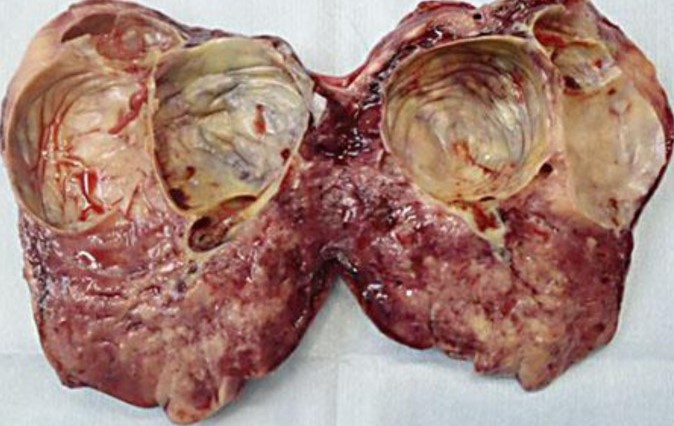

Μακροσκοπική εικόνα δεξιού εξαρτήματος – Καλοήθες νεόπλασμα Brenner (Ευγενική παραχώρηση Dr. V. Penopoulos)